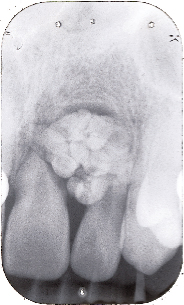

U xơ răng (Odontoma)

Howard liệt các loại u xơ răng vào loại răng dư thứ tư, nhưng cách phân loại này không được chấp nhận một cách rộng rãi. "Odontoma" là thuật ngữ đề cập đến bất kỳ khối u có nguồn gốc từ răng. Tuy nhiên, hầu hết các tác giả đều chấp nhận rằng u xơ răng tương ứng với một dị tật mô thừa (hamartomatous) chứ không phải là một khối u. Tổn thương bao gồm nhiều hơn một loại mô và vì vậy được gọi là odontoma hỗn hợp. Hai loại riêng biệt được mô tả: Các dị tật của mô răng hoàn toàn không theo quy luật, sắp xếp nào được gọi là odontoma phức hợp (Hình 8). Trong khi đó, một loại tổn thương khác là các dị tật của răng mang đặc tính cấu trúc bề mặt tương tự nhau được gọi là một odontoma đa hợp.

Hình 8: X-quang quanh chóp của odontoma tổng phức hợp |

Hình 10: Sư tiêu xương chân răng của răng cửa giữa và bên hàm trên gây ra bởi odontome đa hợp trong hình minh họa 9 |

Bệnh lý học

Sự hình thành nang thân răng (Dentigerous cyst ) là một vấn đề khác có thể liên quan đến các răng dư (Hình 9), Primosch báo cáo túi nang mở rộng ở 30% các trường hợp, nhưng bằng chứng mô học của sự hình thành u nang đã được tìm thấy trong chỉ 4 đến 9% của các trường hợp. Sự tiêu xương của chân răng dư liền kề có thể xảy ra nhưng nó là vô cùng hiếm (Hình 10)